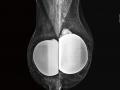

Bases físicas da mamografia